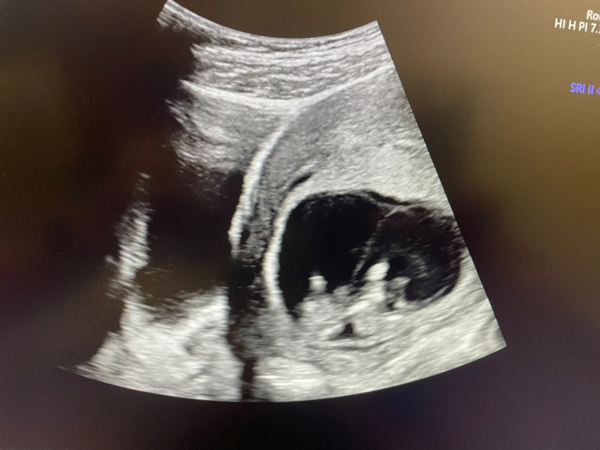

今天懷孕10+周

胎兒大小,心跳及活動力都好棒棒👍

於7周超音波檢查發現有雙胞胎妊娠🧐

目前兩位寶寶都充滿活力💖